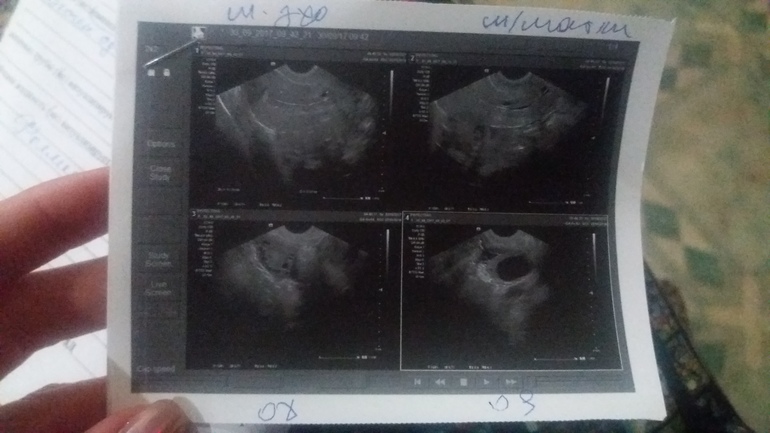

В прошлом цикле после О назначали дюф. Принимала его долго, тк. была бхб... С этого цикла с 5дц принимала прогинову, а с 16дц дюфастон. О отслеживала по узи, она должна была быть на 20дц... Но фолик перерос в кисту 36х33.. Вот и вопрос, что дальше??? Сег...

Сегодня 46 ДЦ. Киста левого яичника тут понятно. Что в матке справа за пятнышко и в шейке какие-то кисты в заключении написано. Врач ничего толком не сказал